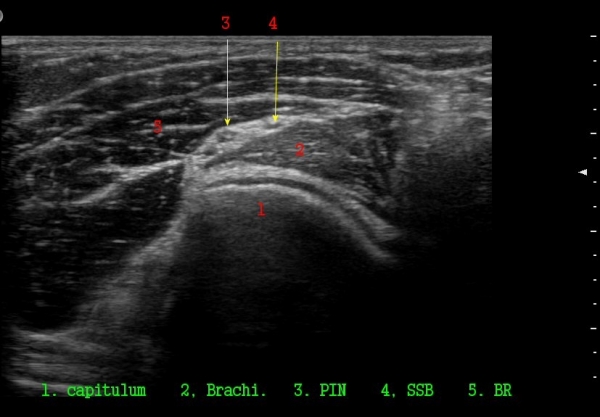

ŽÃËÀÚ¸¦ ¸»´ÜÀ¸·Î À̵¿ÇÏ´Ï ¿ä°ñµÎ ºÎÀ§¿¡¼­ Àú¿¡ÄÚ ³¶Á¾ÀÌ Èİñ°£½Å°æºÐÁö¸¦ Ç¥ÃþÀ¸·Î

ÀüÀ§½Ã۰í ÀÖ´Ù(±×¸² 2, 3,)

Á¾´Ü¸é°Ë»ç¿¡¼­ Àú¿¡ÄÚ ³¶Á¾ÀÇ Ç¥Ãþ¿¡¼­ Èİñ°£½Å°æºÐÁö°¡ ÀüÀ§µÇ¾î °üÂûµÈ´Ù(±×¸² 4, 5, 6).